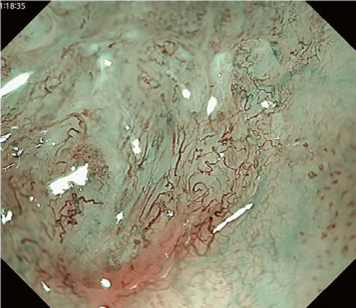

Predicting invasion depth of superficial esophageal squamous cell carcinoma is crucial in determining the precise indication for endoscopic resection (ER) because the rate of lymph node metastasis increases in proportion to the invasion depth of the carcinoma. Previous studies have shown a close relationship between microvascular patterns observed by magnifying endoscopy and invasion depth of the superficial carcinoma. Although there were two major classifications, Inoue and Arima, the Japan Esophageal Society (JES) integrated the two classifications and simplified it and developed a new magnifying endoscopic classification for the characterization and predicting invasion depth of superficial esophageal squamous cell carcinomas (SESCCs). This is essential for developing a treatment strategy for SESCC, in particular the indication for ER. Therefore, in this classification, morphological types of microvessels are classified into two categories of noncancerous [type A: normal epithelium, inflammation, and squamous intraepithelial neoplasia (SIN)] and cancerous (Type B: SCC) lesions. The cancerous types of microvessels corresponding to SESCCs are subclassified into three groups based upon an indication for ER as follows: an absolute indication type (Type B1: T1a-EP or T1a-LPM), a relative indication type [Type B2: T1a-MM or T1b-SM1(tumor invades the submucosa to a depth of 200 μm or less from the muscularis mucosa)], and a contraindication type [Type B3: T1b-SM2 (tumor invades the submucosa to a depth more than 200 μm)]. Diagnostic criteria of the JES classification are based on the degree of microvascular irregularity in the target lesion observed by magnifying endoscopy. Intrapapillary capillary loops (IPCL) are a basic unit of microvasculature in the stratified squamous epithelial layer. The microvascular irregularity is evaluated for the presence or absence of each of the following morphological factors: weaving (i.e., tortuosity), dilatation, irregular caliber, and different shape (i.e., various shapes). Microvessels are classified as type A if they have three or fewer factors (i.e., without severe abnormality; . Fig. 1a) and type B if they have all four (i.e., with severe abnormality). Type B is then subclassified into B1, B2, and B3 (. Fig. 1b–d, respectively) based on the running pattern or degree of dilatation of severely irregular microvessels. The definitions and schemas of type A and B vessels and predicted histology of invasion depth by type B vessels are summarized in . Table 1. A large scale validation study showed high overall accuracy (90.5%) of type B vessels of the JES classification. The most important auxiliary criterion in the JES classification is avascular area (AVA). AVA is defined as a low or no vascularity area surrounded by all subtypes of type B microvessels including B1 vessels. Diameters of AVA are positively correlated with sizes of histological cancer nest and the histological invasion depth of SESCC. Small (<0.5 mm), middle (0.5 ≤< 3 mm), and large (≤3 mm) AVA are suggestive of T1a-EP/ LPM, T1a-MM/T1b-SM1, and T1b-SM2, respectively. A key point to note is that any types of AVA (small, middle, and large) surrounded by B1 vessels are suggestive of T1a-EP or T1a-LPM SCC.